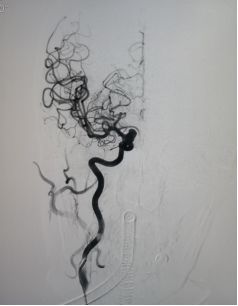

术后6个月复查造影示:动脉瘤不显影,血管重建效果令人满意。

术后6个月复查动脉瘤完全闭塞,局部血管重建。